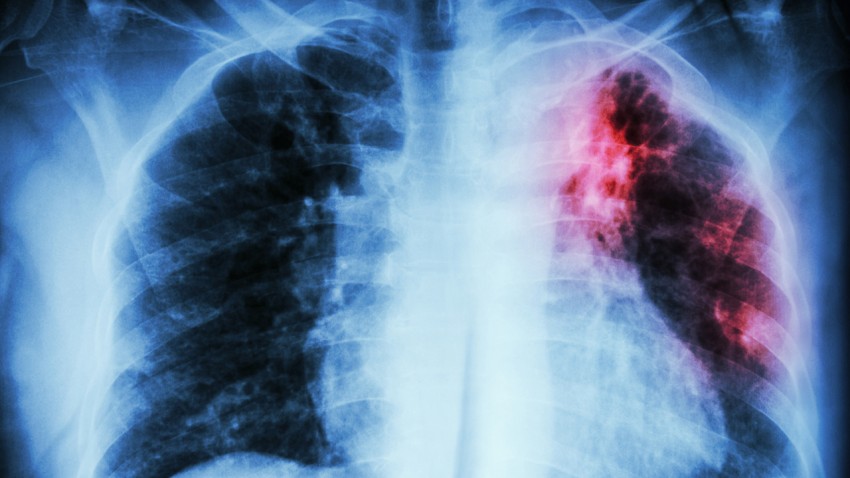

By utilizing chest X-ray imaging and sputum smear tests—an important measure of bacterial load—the study provided a comprehensive view of how metabolism varies with disease severity. Patients with higher bacterial loads exhibited distinct metabolic disruptions, indicating potential biomarkers that could inform future treatment and nutritional strategies.